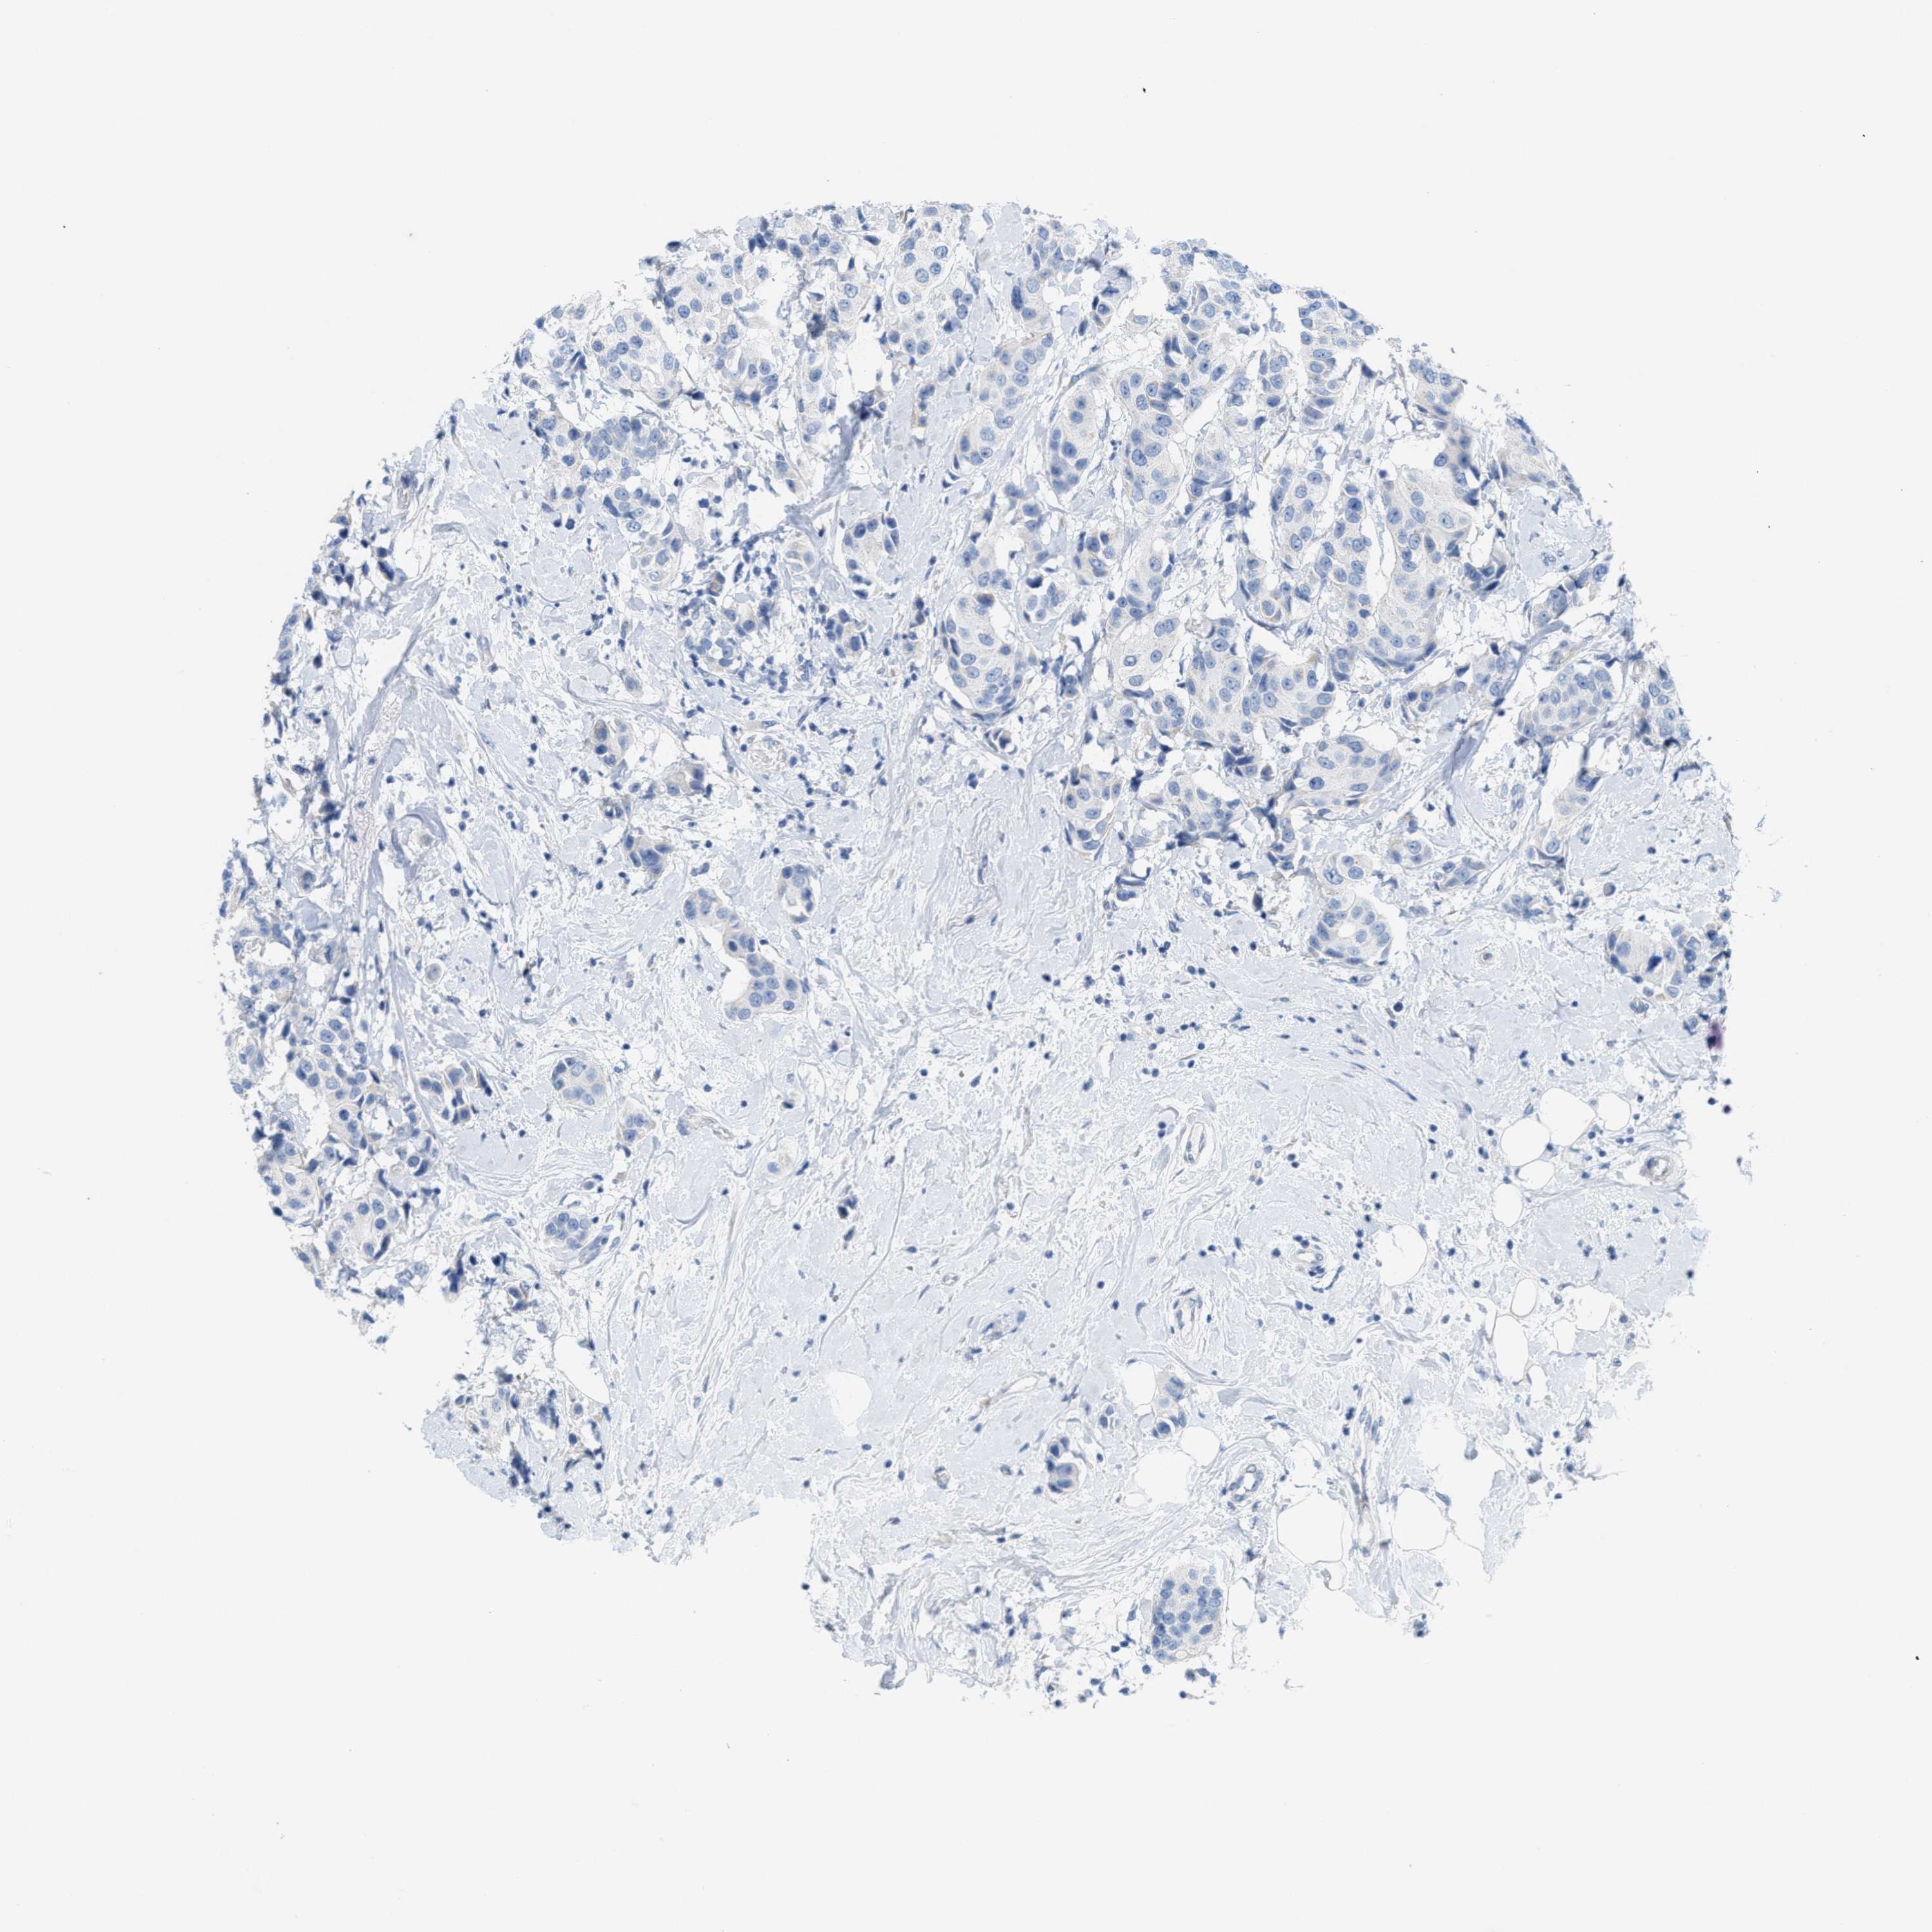

CANCER BREAST CANCER Show tissue menu

BRCA TCGA BRCA VALIDATION PROTEIN EXPRESSION